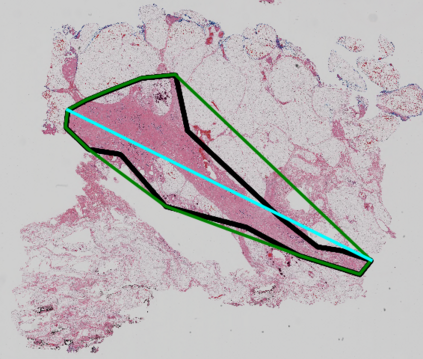

Whole slide images (WSIs) pose unique challenges when training deep learning models. They are very large which makes it necessary to break each image down into smaller patches for analysis, image features have to be extracted at multiple scales in order to capture both detail and context, and extreme class imbalances may exist. Significant progress has been made in the analysis of these images, thanks largely due to the availability of public annotated datasets. We postulate, however, that even if a method scores well on a challenge task, this success may not translate to good performance in a more clinically relevant workflow. Many datasets consist of image patches which may suffer from data curation bias; other datasets are only labelled at the whole slide level and the lack of annotations across an image may mask erroneous local predictions so long as the final decision is correct. In this paper, we outline the differences between patch or slide-level classification versus methods that need to localize or segment cancer accurately across the whole slide, and we experimentally verify that best practices differ in both cases. We apply a binary cancer detection network on post neoadjuvant therapy breast cancer WSIs to find the tumor bed outlining the extent of cancer, a task which requires sensitivity and precision across the whole slide. We extensively study multiple design choices and their effects on the outcome, including architectures and augmentations. Furthermore, we propose a negative data sampling strategy, which drastically reduces the false positive rate (7% on slide level) and improves each metric pertinent to our problem, with a 15% reduction in the error of tumor extent.